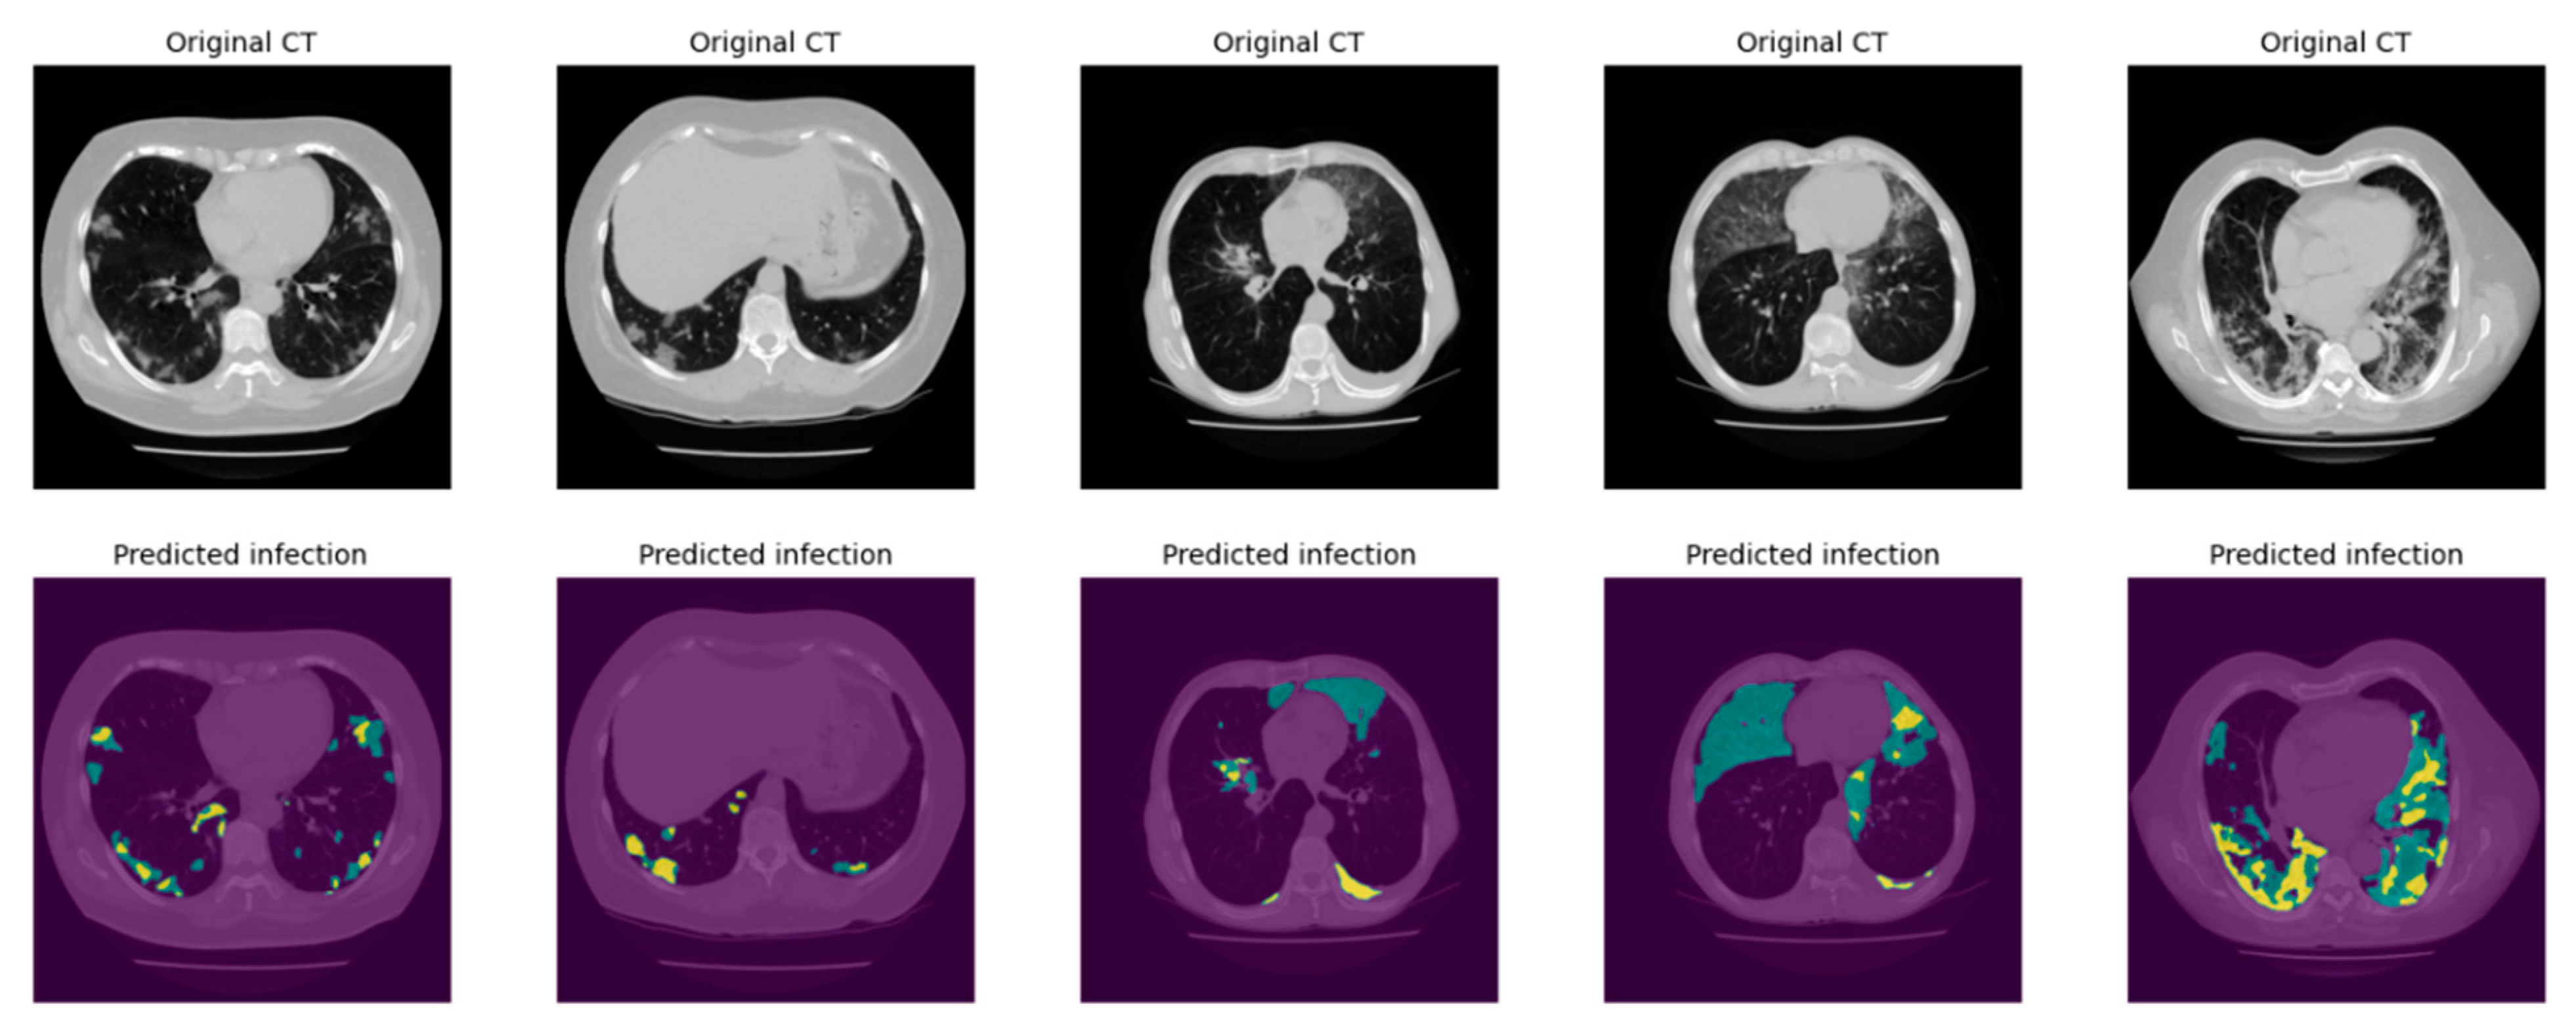

2.3.2. Infection Area Segmentation

2.3.3. Segmentation of GGO and Consolidation Patches

2.3.4. Integrated Model and GUI